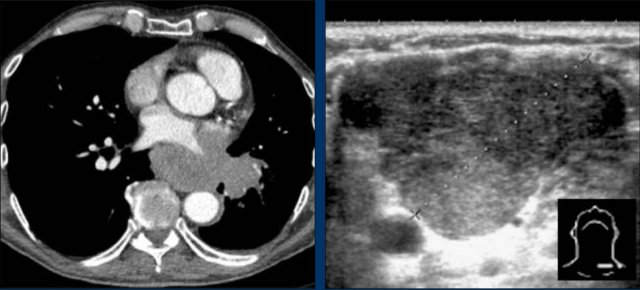

Postoperative Pericardial Hemorrhage

In patients with recent cardiac surgery, a sudden change in heart size on chest X-ray should raise suspicion for pericardial bleeding, which may be life-threatening.

Case Example 2:

• A postoperative patient showed a change in the cardiac silhouette.

• Echocardiography detected only a minimal pericardial effusion.

Case Example 2 - CT imaging

• CT imaging revealed a large posterior pericardial effusion compressing the left ventricle (blue arrow: effusion; red arrow: compressed, contrast-filled left ventricle).

• Surgical exploration confirmed a large posterior pericardial hematoma.

Note

: Minimal anterior fluid on ultrasound may underestimate the true volume if the effusion is loculated posteriorly, highlighting the value of CT in postoperative cases.

Especially in patients who had recent cardiac surgery an enlargement of the heart figure can indicate pericardial bleeding.

This patient had a change in the heart configuration (importance of prior imaging) and pericardial bleeding was suspected.

Ultrasound demonstrated only a minimal pericardial effusion.